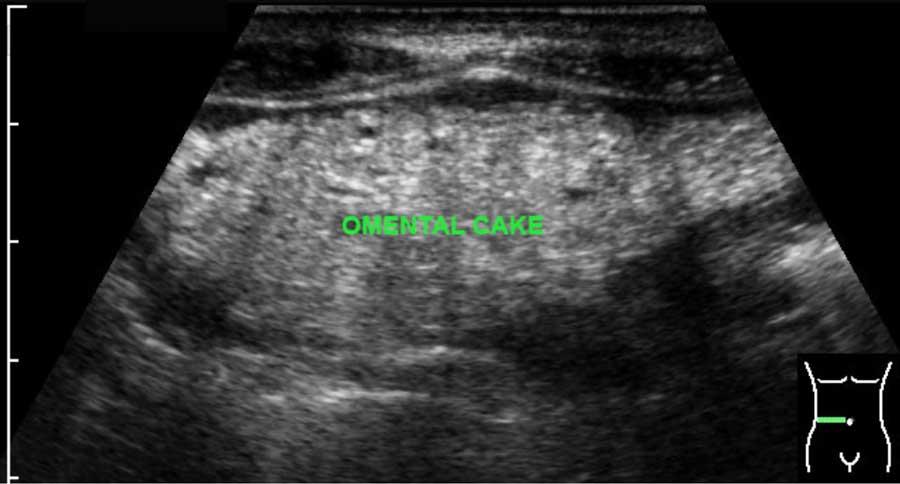

The normal omentum is usually not separately visible.

Khi nó dày lên, ví dụ trong viêm phúc mạc ác tính hoặc hiếm gặp hơn là viêm phúc mạc do lao, nó có thể biểu hiện dưới dạng bánh mạc nối, đặc biệt khi có cổ trướng đi kèm.